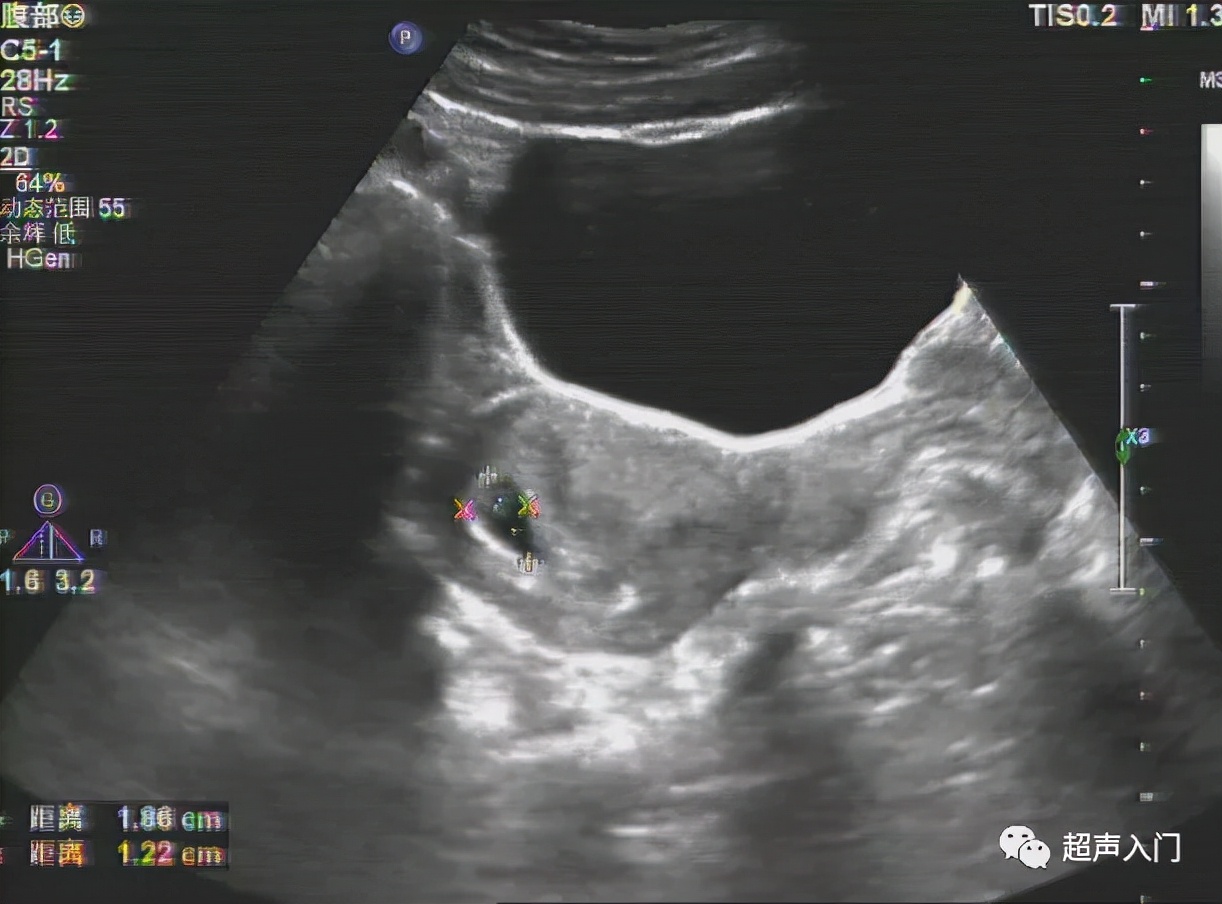

前位子宫(前倾前屈,经腹纵切面)

前位子宫(前倾前屈,经阴道纵切面)